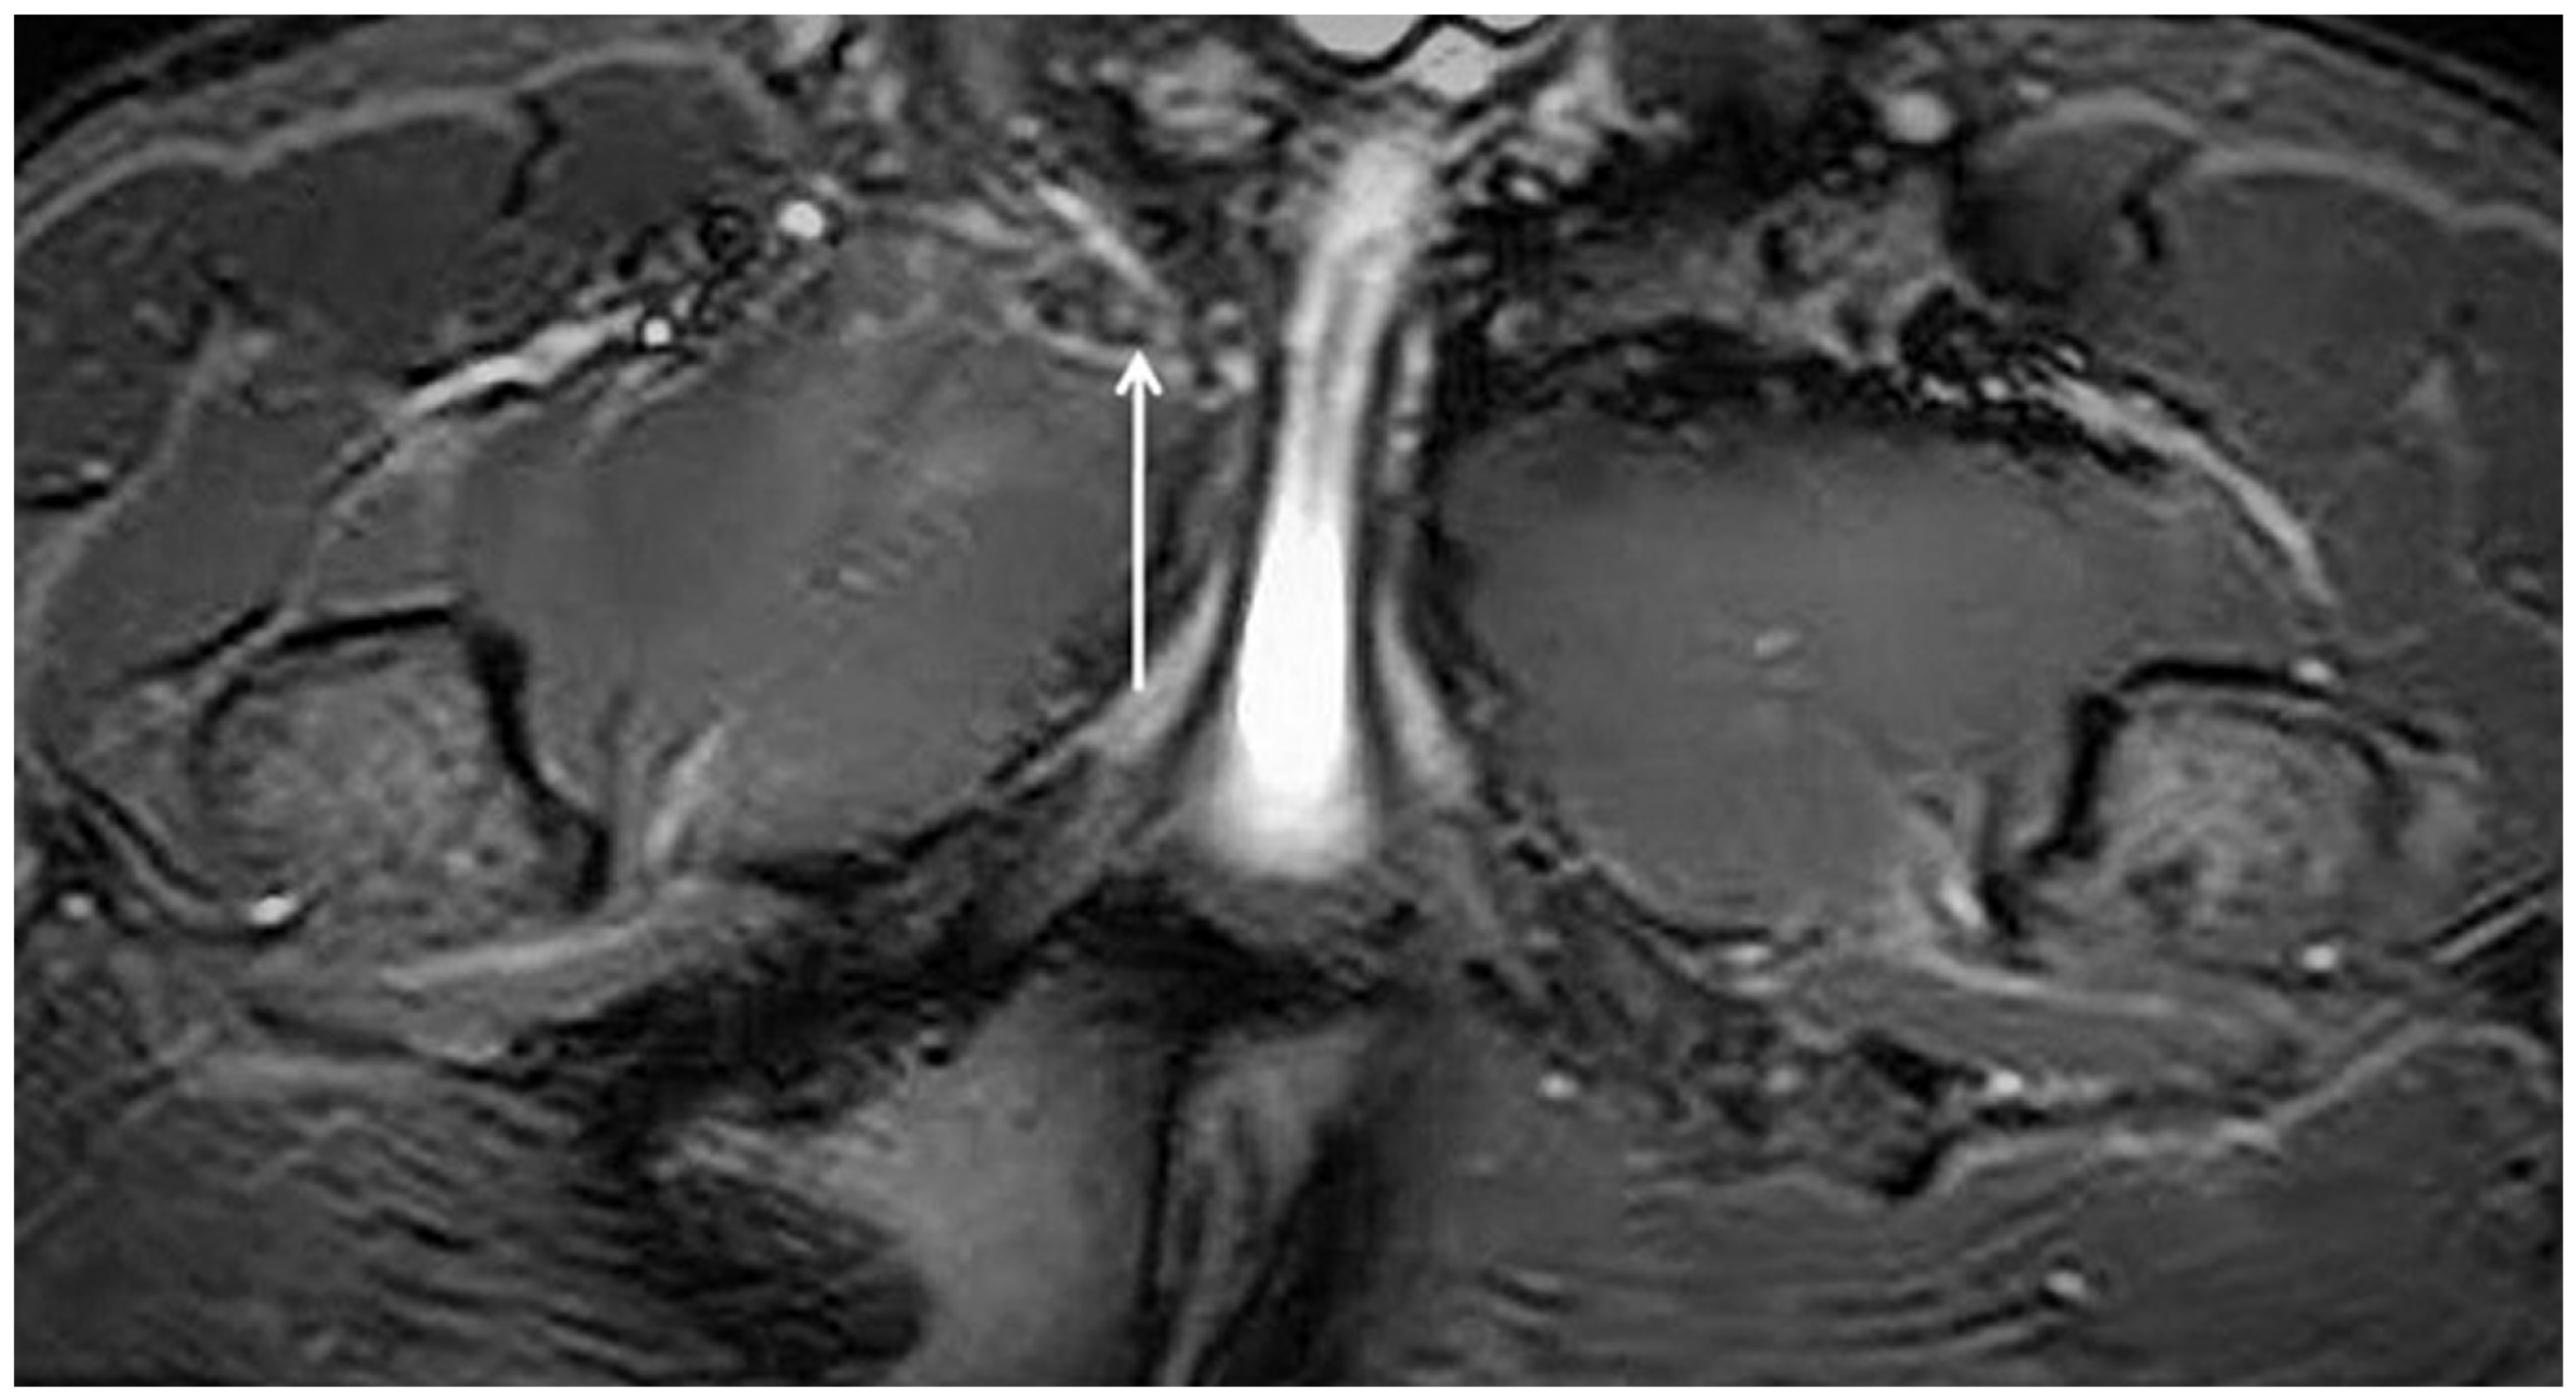

3.3. Magnetic Resonance Imaging